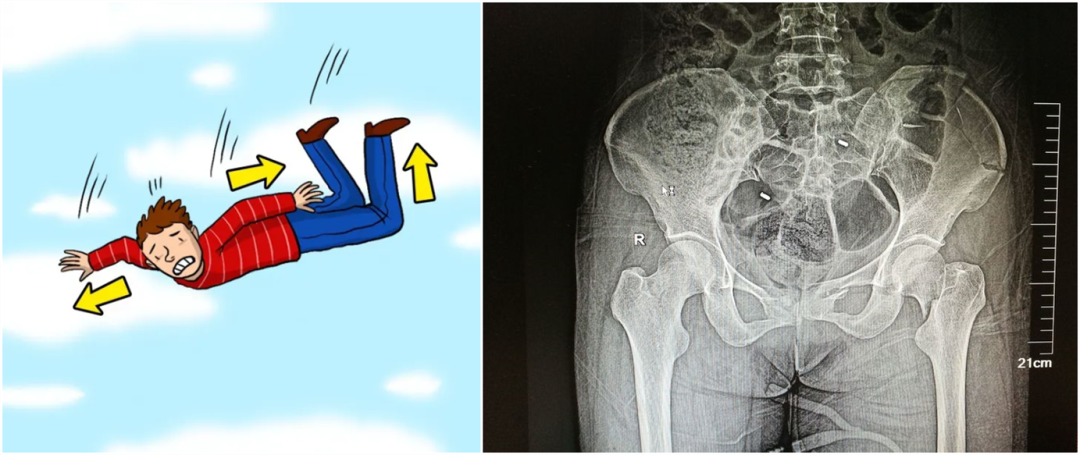

從暴力的大小來看,還可以細分為高能量的損傷和低能量的損傷。比如說,如果是車子撞的,從高處墜落,通常會造成高能量的損傷,而普通的跌倒造成的骨折,一般不太嚴重,可以說是低能量的損傷。

【醫(yī)療科普】:不穩(wěn)定性骨折影像

不穩(wěn)定性骨折